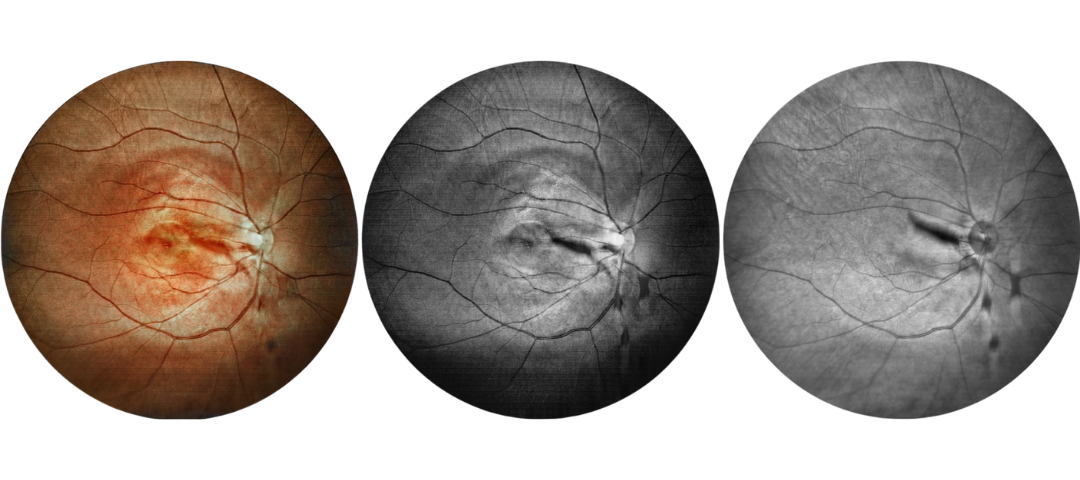

Scanning Laser Ophthalmoscope Obtain Retinal Layer and Choroidal Layer

Our scanning laser ophthalmoscope uses multi-wavelength laser scanning to penetrate the fundus, capture details of the retinal and choroidal layers, and obtain high-definition fundus images.

Retina Examination Under Cataracts

Examining fundus diseases through cataracts is a crucial topic in ophthalmology. Traditional fundus cameras cannot see through cataracts to capture fundus conditions. However, our DF600 scanning laser ophthalmoscope can penetrate moderate cataracts, providing a glimpse into the fundus and offering greater convenience for fundus examinations in patients with cataracts.

Fundus Cases Display

Our SLO makes fundus examination easier for you, capturing ultra-clear and wide-angle images of the retina and choroid, and then synthesizing color fundus images to present a rich picture of the fundus status.

Diabetic retinopathy: post photocoagulation

Diabetic retinopathy: bleeding and microvascular lesions

Diabetic retinopathy: post photocoagulation

Diabetic retinopathy: bleeding, exudation, and post-photocoagulation

Diabetic retinopathy: bleeding

Diabetic retinopathy: bleeding and exudation

Diabetic retinopathy: vascular abnormalities, bleeding spots, and post-photocoagulation

Diabetic retinopathy: bleeding, exudation and choroidal vascular abnormalities

High blood pressure, venous obstruction, and bleeding